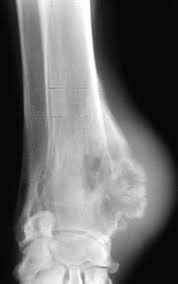

Cancer is not just one entity—it is any process of uncontrolled cell growth. There are three main forms of bone cancer, but the most common and aggressive is osteosarcoma, which accounts for up to 95% of all cancer diagnoses. Cancer in cats is the leading cause of death among cats. But i don't know that we have the answer for what causes most cancers in cats. Read on to learn 10 facts about cancer in cats. It is a tumor that often affects the long bones. There may also be some soft issue involvement. What you should know about osteosarcoma (bone cancer) in cats a type of bone cancer called osteosarcoma is the most common type of primary bone cancer, accounting for over 95% of all bone tumors.

Some tumors may grow slowly and do not typically spread, called benign, while others will act aggressively called malignant. We do know people are keeping cats longer. For every type of cell in the body, from your cat's skin to her stomach and blood vessels, there is a corresponding type of cancer. Limbs (upper arm and upper leg bones) pelvis (hipbones) rib cage. The connective tissue that is found between the bones and joints. Cats can get many different kinds of cancer, but the ones that most commonly affect kitties are lymphosarcoma, squamous cell carcinoma, and mammary (breast) cancer. For example, lymphoma affects the lymphatic system, while osteosarcoma affects bone. Osteosarcoma is also the most common bone tumor in cats, but the behavior of this tumor type is less aggressive than in dogs.

The rate of metastasis at the time of diagnosis is low.

This tumor typically occurs in the arm near the shoulder and in the leg near the knee in children, adolescents, and young adults but can occur in any bone, especially in older adults. The rate of metastasis at the time of diagnosis is low. It is seen more often in large breed cats. This cancer can lead to bone disintegration and may spread into the soft tissues surrounding the affected bone. A cat's mouth, similar to our own, is made up of several different cell types; It is a tumor that often affects the long bones. It is the most common oral cancer in cats. Squamous cell carcinoma is a highly aggressive form of oral cancer in cats, and it can be difficult to detect since felines are notoriously furtive about showing signs of illness. But i don't know that we have the answer for what causes most cancers in cats. Like humans, cancer in cats manifests as tumors. An oral tumor is an abnormal growth of cells. There are many types of cancer in cats. It is caused by uncontrolled cell growth, and affects a wide range of cell types and organs in the body.